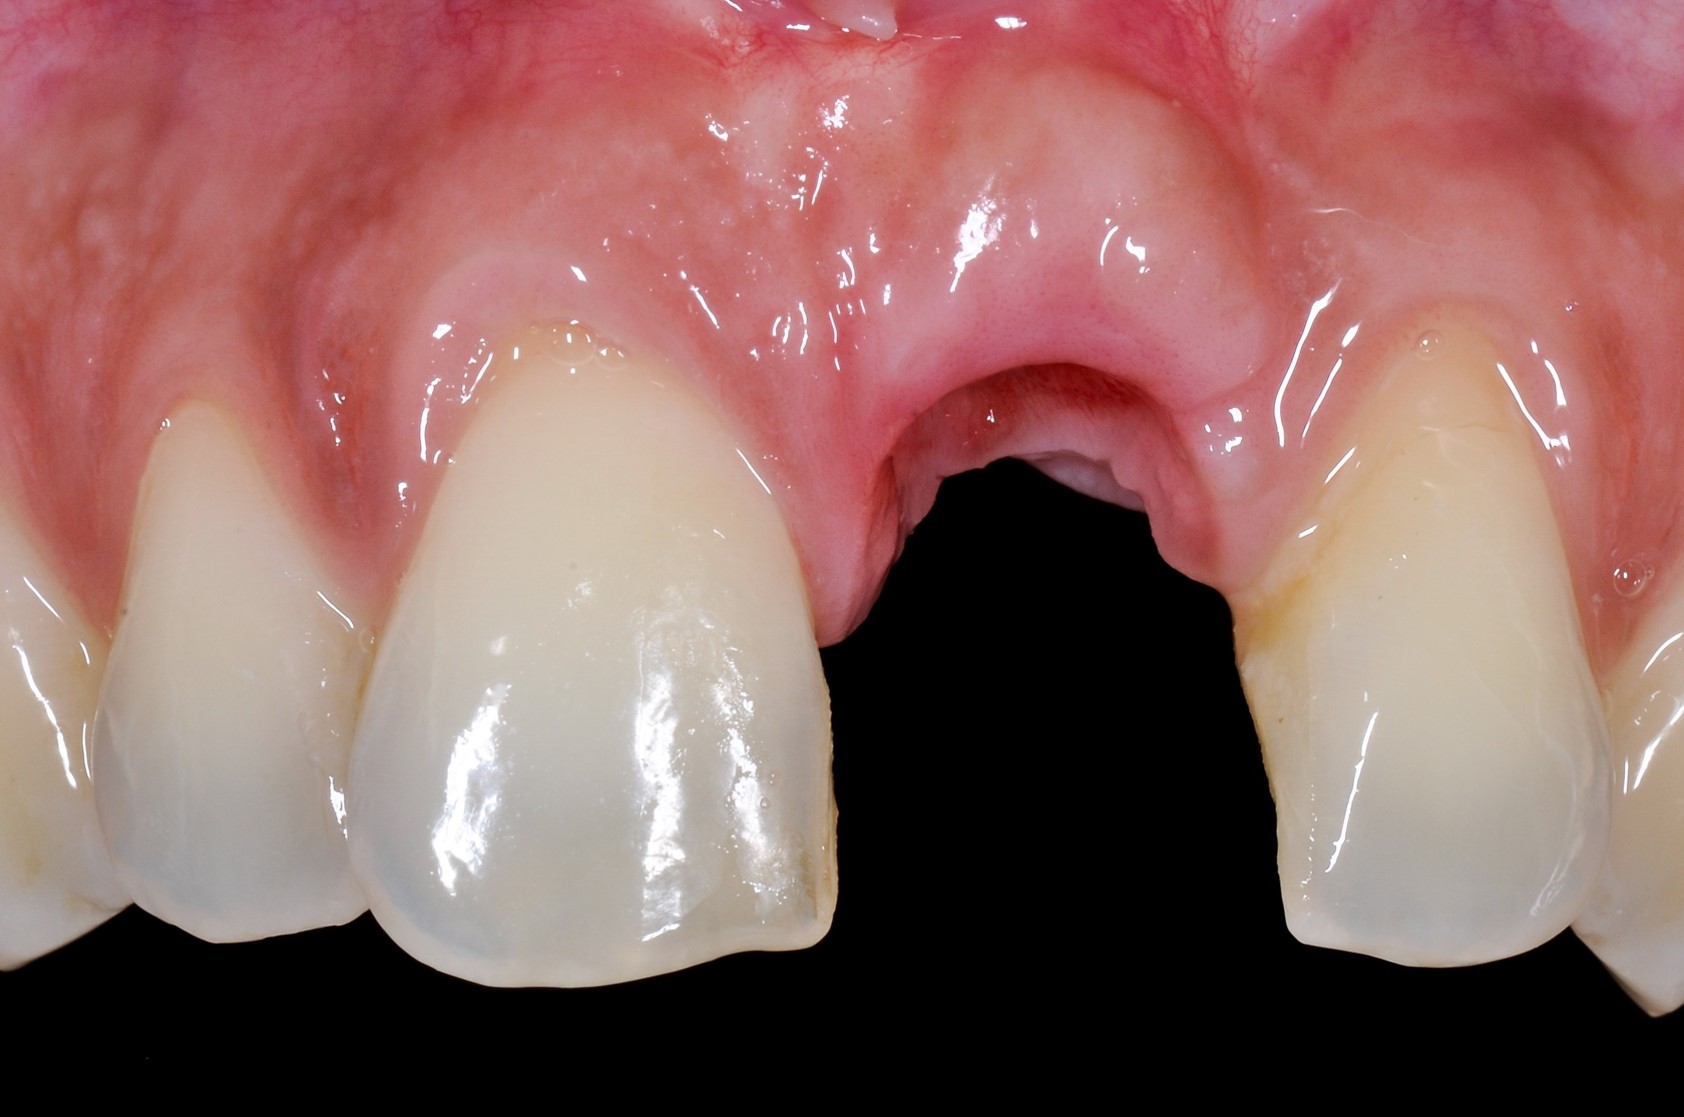

Immediate implant placement with cerabone® and mucoderm® - Dr. F. Rossi - recession on tooth 11Immediate implant placement with cerabone® and mucoderm® - Dr. F. Rossi

recession on tooth 11